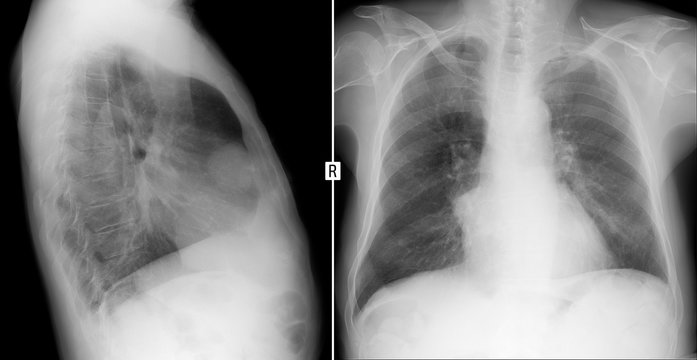

Рентгеновские снимки тератомы средостения: Диагностика и лечение

Раздел: Фотоэссе